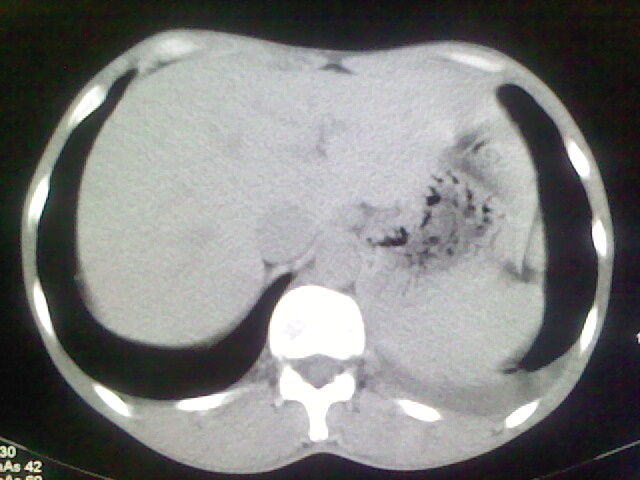

以下是引用杀毒软件在2008-9-3 6:11:00的发言:[br]侵袭性胸腺瘤------一般不侵到气管旁[br][br]考虑----纵隔淋巴瘤,心包及胸膜受累

以下是引用随光逐影在2008-9-3 7:07:00的发言:[br]1)考虑淋巴瘤可能。2)双侧胸腔积液(以左侧为甚)。3)心包积液。